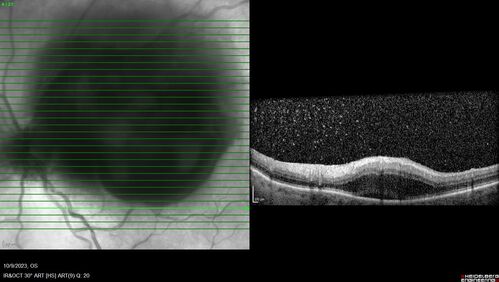

Ruptured Retinal Arterial Macroaneurysm - Submacular hemorrhage and BRAO

81 year old female with vision loss for a few days. Coumadin was high with INR at 3.1 VA 6/200